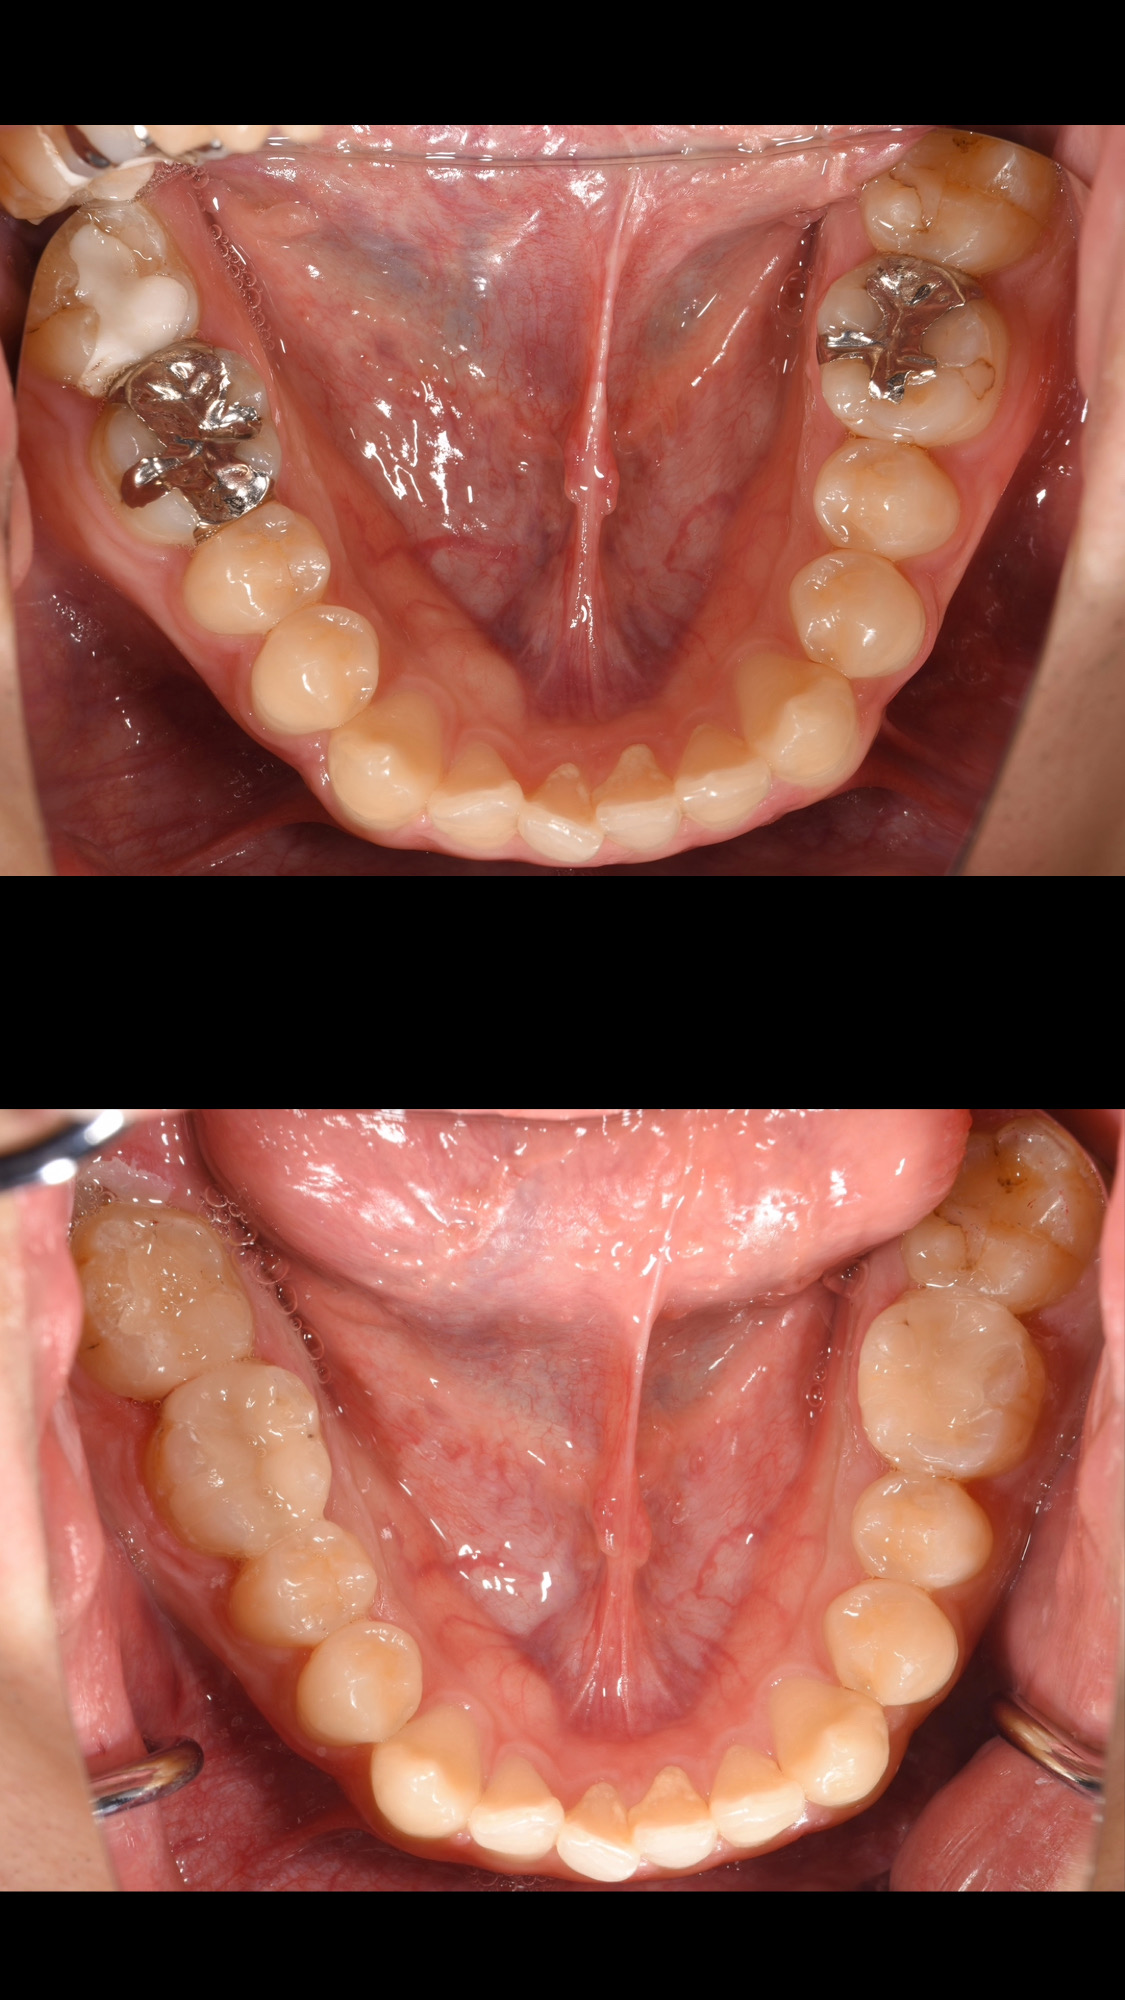

銀歯の色を気にされていたため、セラミックインレーで治療しました。

2回目来院時に8本まとめて銀歯、銀歯の下の虫歯を除去し、セラミックインレーの型取り。

3回目来院時に8本まとめてセラミックインレーのセットを行いました。

銀歯の適合が悪く、銀歯を除去すると全ての歯が虫歯になっている状態でしたので、歯を守るためにも治療を行ってよかったケースです。